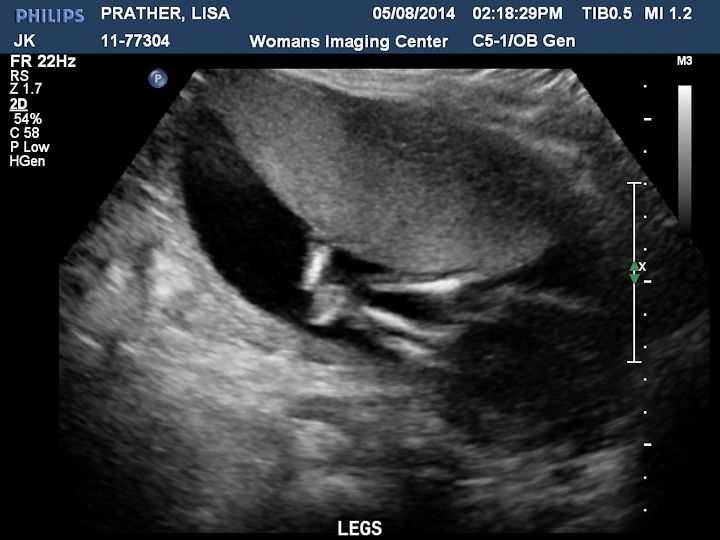

Here are some pictures we got. There is a description on each picture of what you are looking at.

This is my favorite picture, two legs and feet. So cute!